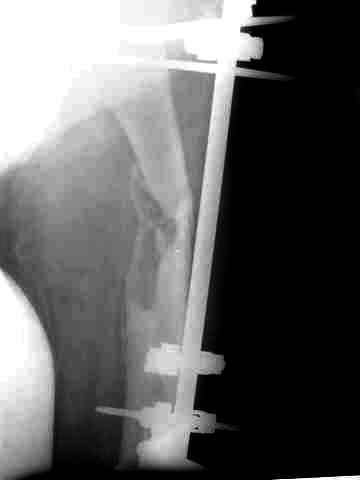

После нескольких некрэктомий, проведения аутодермопластики и заживдения ожоговой раны через 2 месяца после травмы произведен открытый остеосинтез левой бедренной кости штифтом и пластиной (деротационной) [image 01, 02]. Через 1 год и 7 месяцев после травмы у больного диагностированы ложный сустав и хронический остеомиелит левой бедренной кости. Произведено удаление металлических фиксаторов, секвестрэктомия и остеосинтез бедренной костивнешним двухплоскостным стержневым аппаратом [image 03, 04] .

Через 3 года после травмы констатировало отсутствие консолидации бедренной кости, сохранение признаков хронического остеомиелита (свищ в нижней трети левого бедра). Произведен демонтаж аппарата, реостеосинтез бедренной кости спице-стержневым аппаратом, некрсеквестрэктомия. В аппарате удалось лишь частично произвестиустранение углообразной деформации бедренной кости [image 05] .